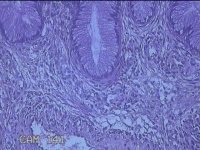

宫颈赘生物

性别

女

年龄

41岁

临床诊断

1.稽留流产 2.慢性宫颈炎

一般病史

停经2个月,阴道流血5天。

标本名称

大体所见

灰白粉红色肿物1.5x0.7x0.3cm一个,表面光滑。

息肉,上皮呈分泌反应